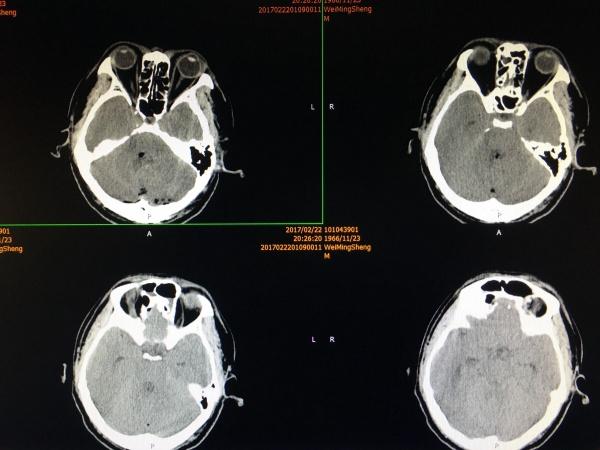

果然如我们术前预料,两侧的小脑后下动脉完整包绕在肿瘤组织之中,以超声刀和吸引器小心分离(见上图中两根迂曲的动脉),分离完整后才是最困难的,我们需要在两根迂曲血管的间隙中继续向下分离至脑干(延髓),万幸!肿瘤与延髓表面有明确的分界,所以考虑室管膜瘤可能大,而术中的冰冻也证明了我们的想法.